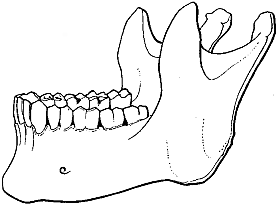

Ein gebücktes Mütterchen ist uns das Abbild des Alters. Ein gerunzeltes, zahnloses Mütterchen. Das Fettgewebe, das die Haut einst prall erhalten, ist geschwunden, und in Falten legt sich die Haut. Die bindegewebigen Bänder, die die Knochen der Wirbelsäule fest aneinander gebunden hatten, haben ihre Elastizität eingebüßt wie ein viel gebrauchtes Gummiband. Und die Wirbelsäule gibt dem Druck des Oberkörpers nach, der Oberkörper sinkt nach vorne. (Abb. 13). In den Kiefern schwindet der Teil, in dem einmal die Zähne gesessen, und die Zähne fallen aus (Abb. 14 u. 15).

|  |

| Abb. 14. Unterkiefer eines erwachsenen Menschen. Nach Toldt. | Abb. 15. Unterkiefer eines alten Menschen. Nach Ribbert. |